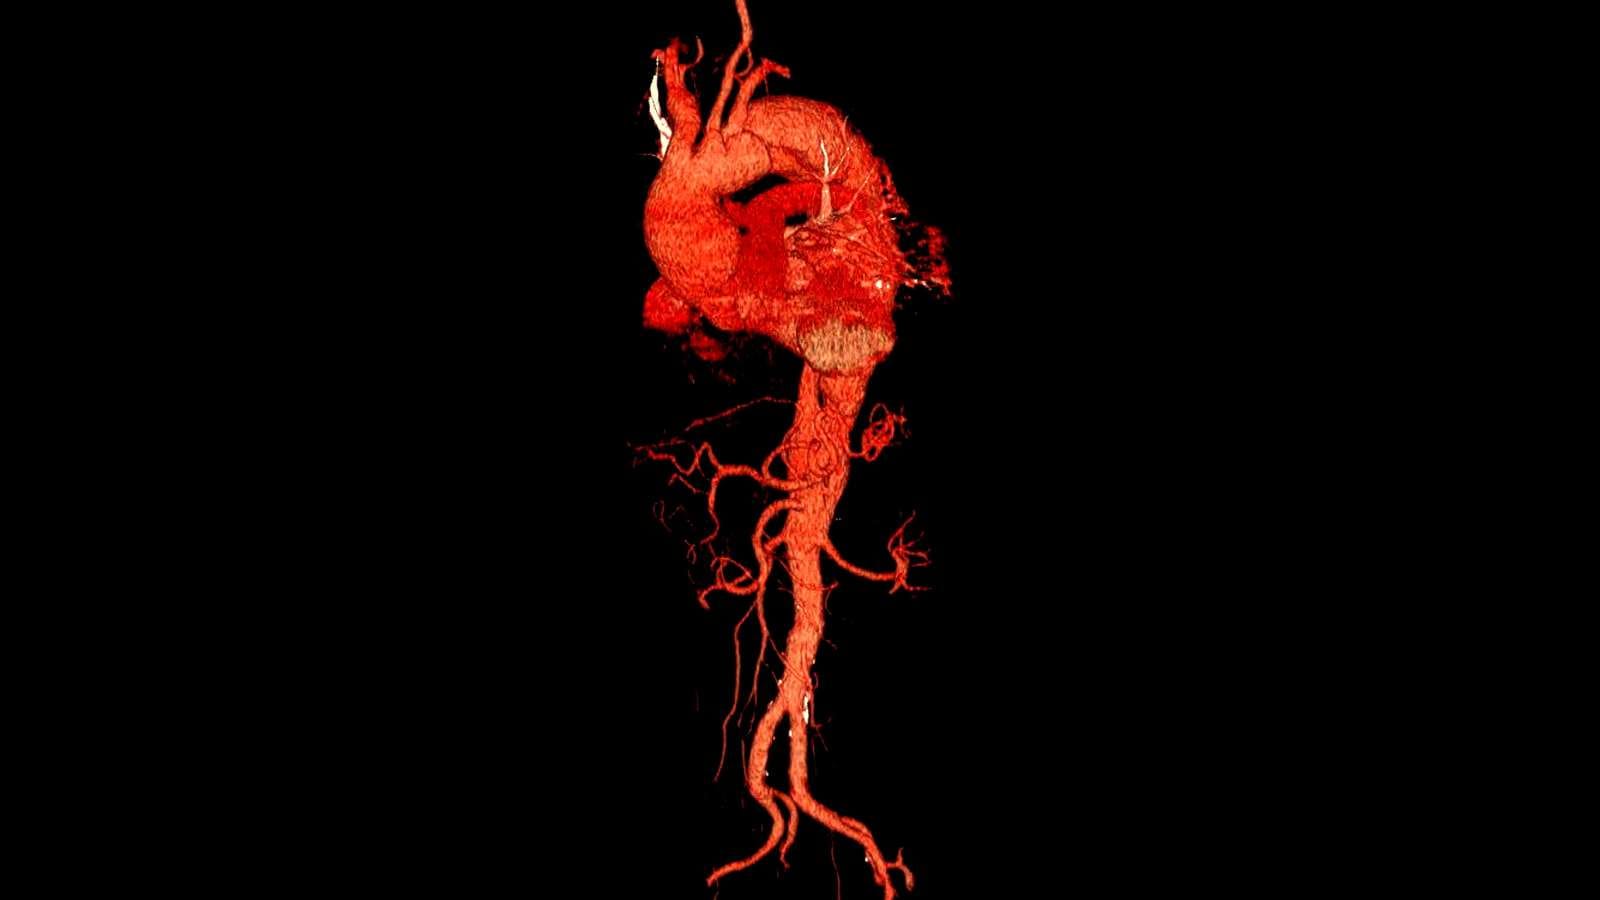

Bağırsak dalak anevrizması embolizasyonu

Embolizasyon

Dev dalak damar anevrizması kaplı stent ile tedavisi

Stent

Böbrek damarı anevrizmasının akım yönlendirici stent ile tedavisi

Stent

Y stent eşlikli kapalı anevrizma tedavisi

Vakalar